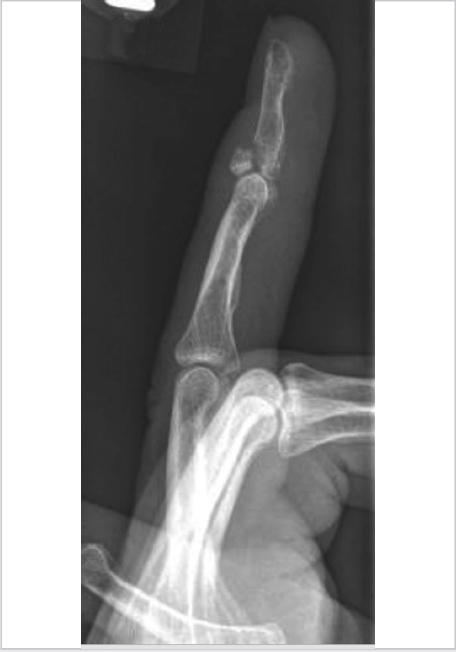

A variety of fixation options exist for bony mallet fractures involving the distal phalanx (► Fig. 35.1), including percutaneous fixation and internal fixation.